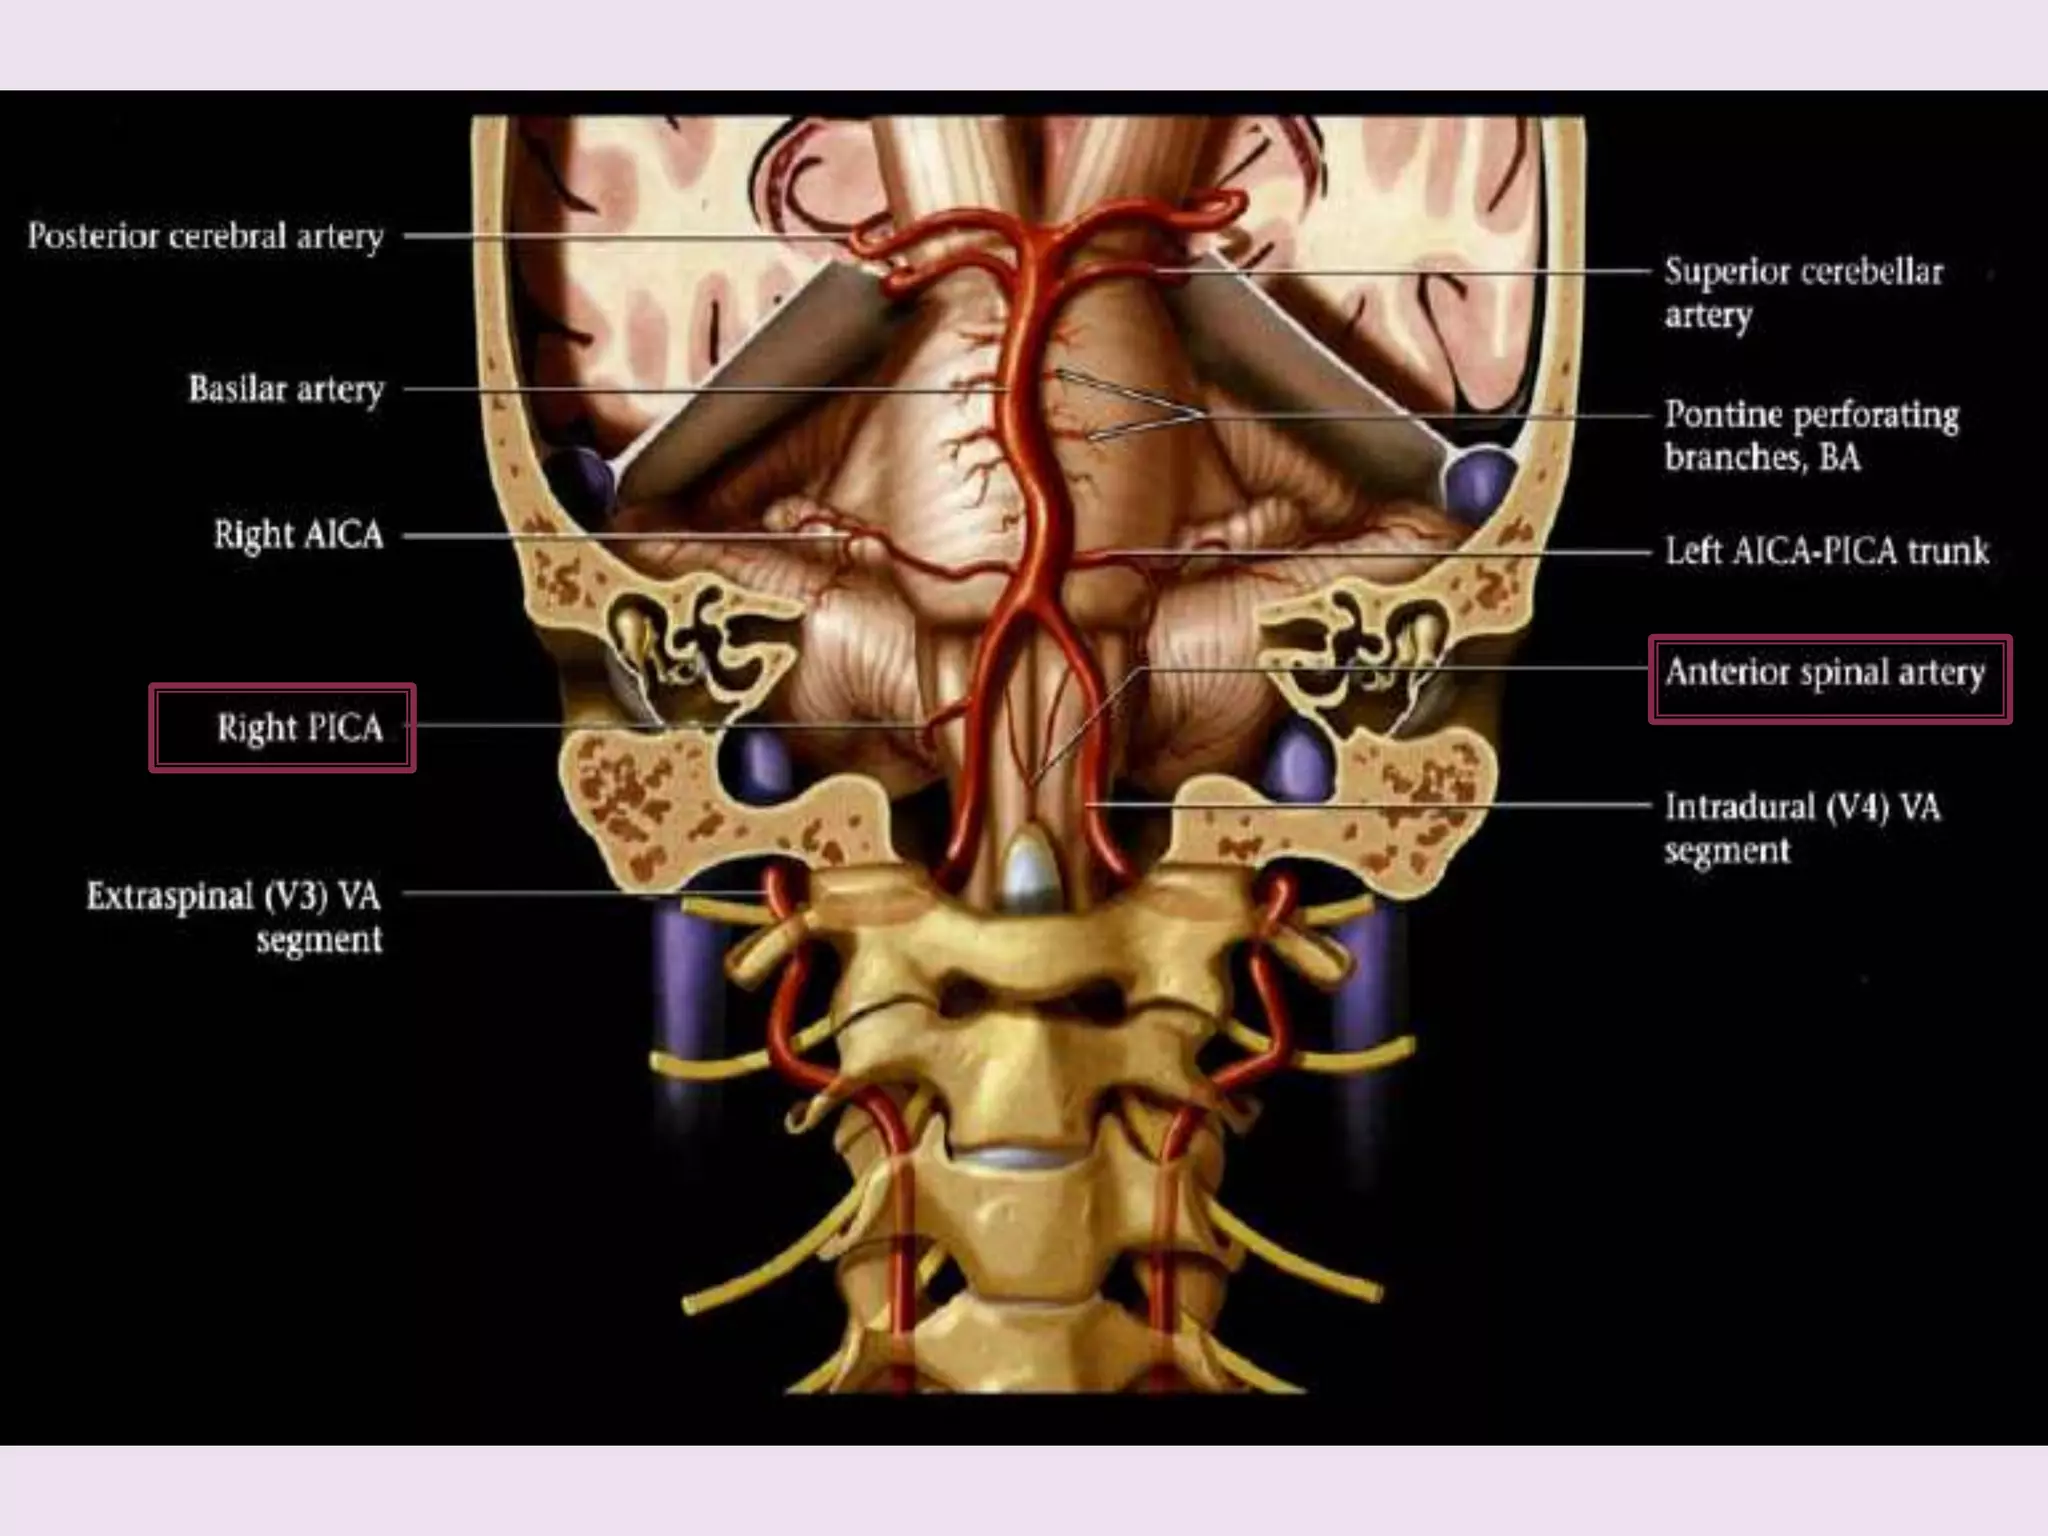

Vertebral artery

Anterior spinal artery

Joins ASA from opposite VA

along anteromedial sulcus of

cervical cord.

Medial medullary

syndrome

Posterior inferior

cerebellar artery

Arises from distal VA

Lateral medullary

Right and left VA s

unite – BA

Course cephalad in front

of pons

Pontine cistern in the

space delineated by

lateral margin of clivus

and dorsum sellae

Terminates in

interpeduncular cistern

Divides into PCAs

•Average length – 3 cm

•Width 1.5- 4 mm

•Diameter <4.5 mm

1. AICA – Anterior Inferior

 1st major branch.

 Posterior laterally in

cerebellopontine angle cistern

toward the internal auditory

canal. Here typically

anteroinferior to facial and

vestibulocochlear nerve.

 Few mms from origin AICA

crossed by abducens nerve.

 Supplies-

▪ Nerves

▪ Inferolateral pons

▪ Middle cerebellar peduncle

▪ Flocculus

▪ Anterolateral cerebelllar hemisphere

2. SCA- Superior Cerebellar

Artery –

 Arises from BA apex.

 Posterolaterally around Pons

and mesencephalon below

tentorial incisura and CNS 3 n

4.

 Supplies –

▪ Superior surface of vermis n

cerebellar hemisphere.

▪ Deep cerebellar white matter.

▪ Dentate nucleus.

 Perforating branches – short

n long segment

 BA – terminates into PCA s